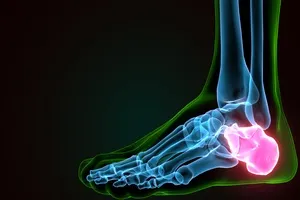

4. 족저근막염

발바닥 아래를 지나는 근막에 염증이 생겨 발생하는 질환으로, 과도한 운동이나 잘못된 자세 등으로 인해 발생할 수 있습니다. 주로 아침에 첫 발을 내딛을 때 심한 통증이 느껴지며, 휴식, 냉찜질, 스트레칭, 맞춤 깔창 등 보존적인 치료를 통해 증상 완화를 기대할 수 있습니다.